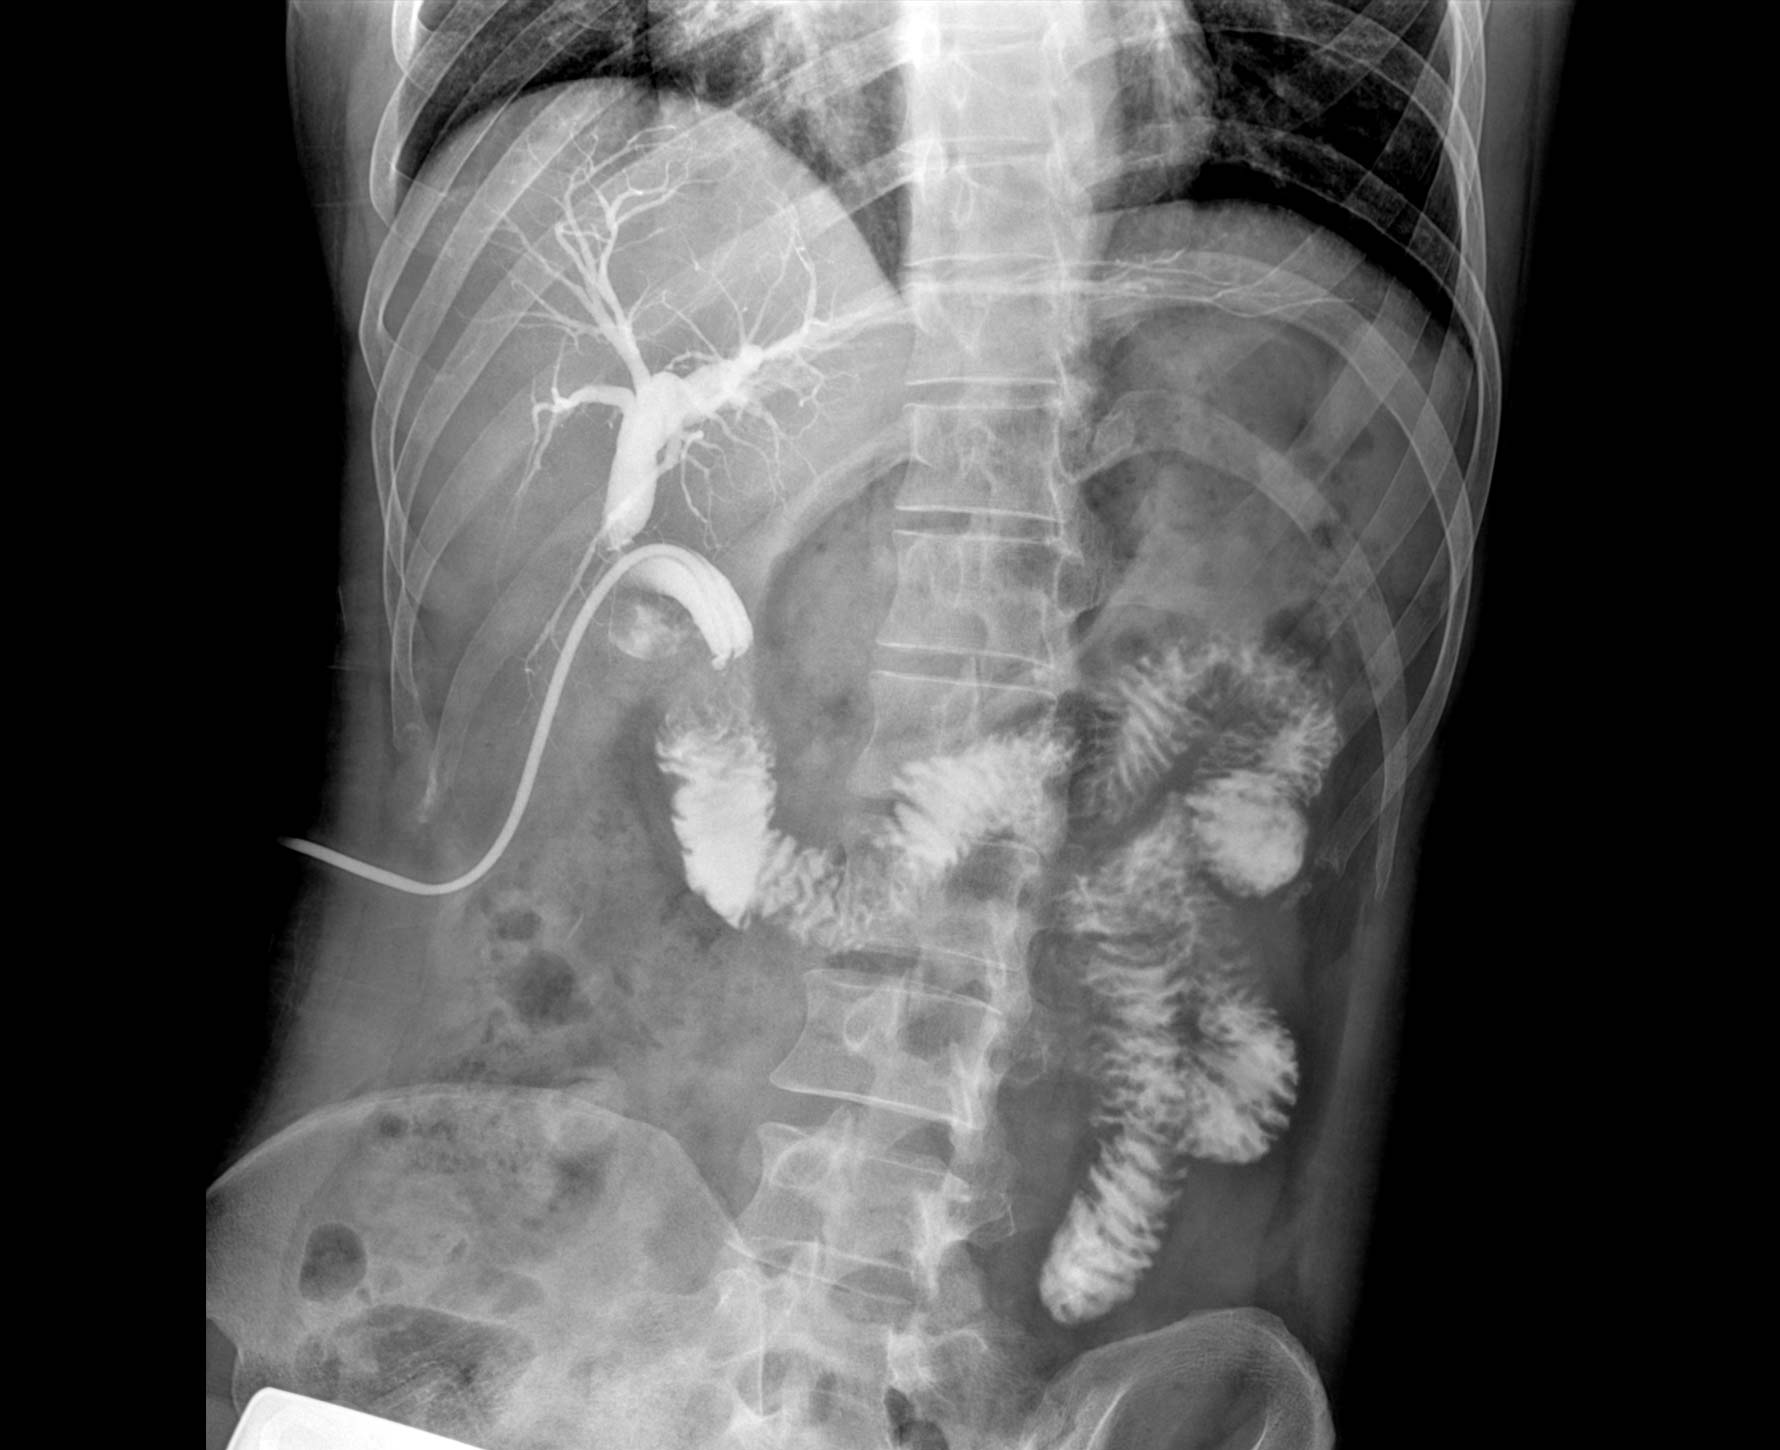

临床图像